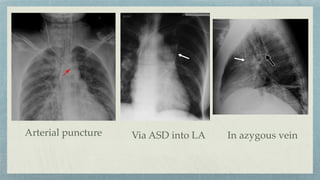

Arterial puncture Via ASD into LA In azygous vein

Complications:-

Pneumothorax

Hemothorax

Infusothorax

Arrhythmia

Infection

Arterial placement

Venous perforation